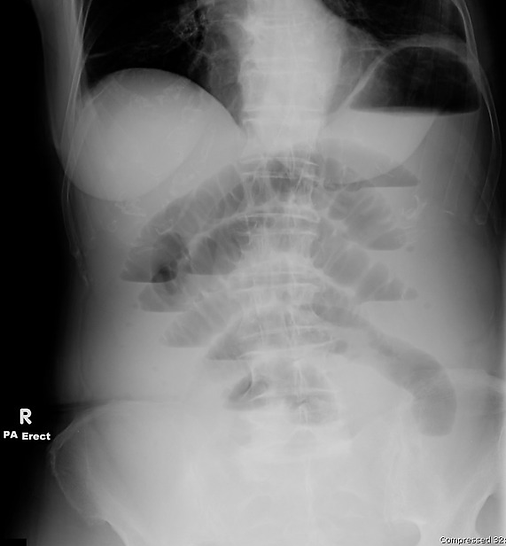

Frontal erect

Abnormal gas: The erect film reveals multiple air–fluid levels in the dilated small bowel loops (visible as air-fluid interfaces at different heights). There is no free air under the diaphragm, so no evidence of perforation.

The dilated small bowel loops are predominantly central. By the 3-6-9 rule (normal diameter: <3 cm small bowel, <6 cm colon, <9 cm cecum), these loops are clearly abnormal (much >3 cm). They stack in a “step-ladder” appearance on the erect film. The large bowel is collapsed (“empty colon sign”), confirming an obstruction proximal to the colon. There is no obvious visible transition point on the plain film, but the context and collapsed large bowel suggest it is likely at the distal ileum or ileocecal valve (common in adhesional obstruction). The bowel walls are not thickened on X-ray, and there are no pneumatosis (air in the bowel wall) signs.

“Oh no!” red flags: The key red flag for bowel perforation which is free intraperitoneal air is absent (no subdiaphragmatic air on the erect film. There is also no evidence of strangulation (no pneumoperitoneum, no gas in the bowel wall, no portal venous gas on this plain film). However, the multiple air-fluid levels and distended loops confirm a mechanical small bowel obstruction.

The abdominal X-rays demonstrate multiple distended loops of small intestine with air-fluid levels, and a collapse of the large bowel, consistent with a Small Bowel Obstruction (SBO). Given the patient’s history of prior abdominal surgery, the most likely cause is adhesions (scar tissue causing obstruction). There are no signs of perforation on the radiograph.